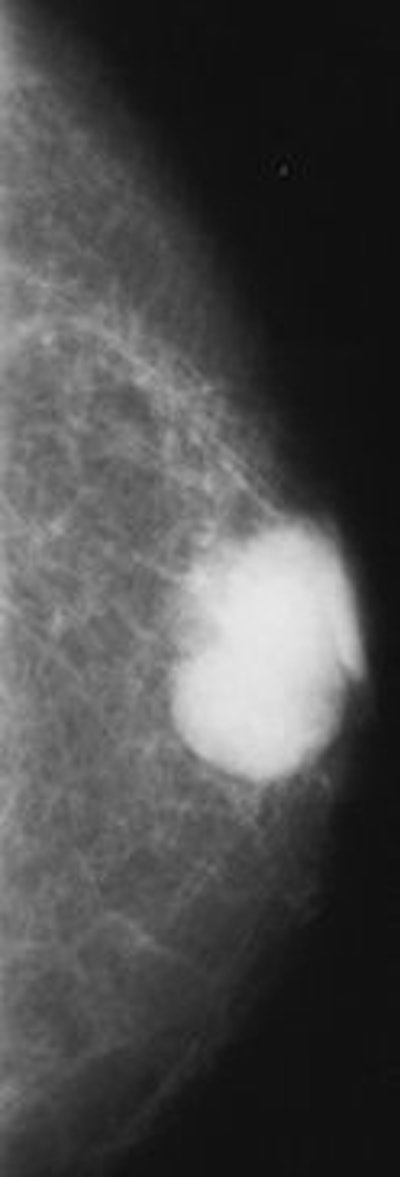

| Infiltrating ductal carcinoma. Above left, craniocaudal mammogram shows a lobulated mass with a primarily well-defined margin and eccentrically located relative to the nipple. Above right, craniocaudal mammogram shows a retroareolar mass with ill-defined margins and nipple retraction. Figure 8,9. Appelbaum AH, Evans GFF, MB, Levy KR, Amirkhan RH, Schumpert TD, "Mammographic Appearances of Male Breast Disease." RadioGraphics. 1999;19(3):559-568. | |